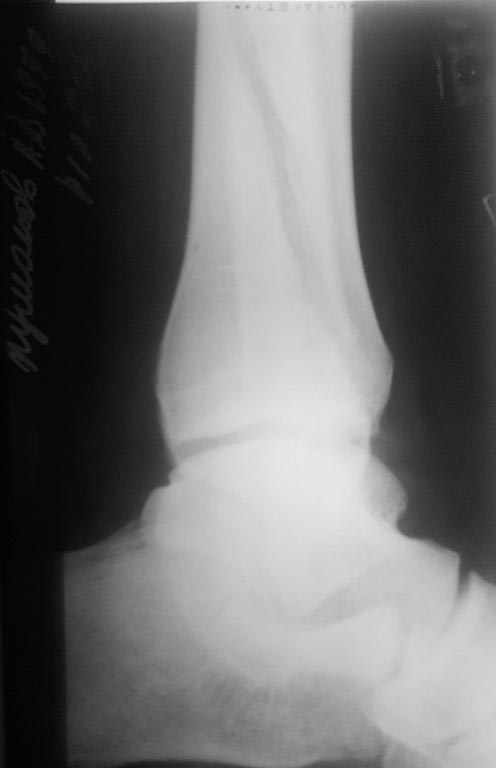

Перелом наружной лодыжки с разрывом ДМС и дельтовидной связки и подвывихом стопы. Пациенту 17 лет, полного телосложения. На контроле сохраняется небольшой подвывих стопы.

Шов дельтовидной связки не выполнялся. Так оставлять или реостеосинтез? Интересует дальнейшая тактика. Смущает молодой возраст пациента...